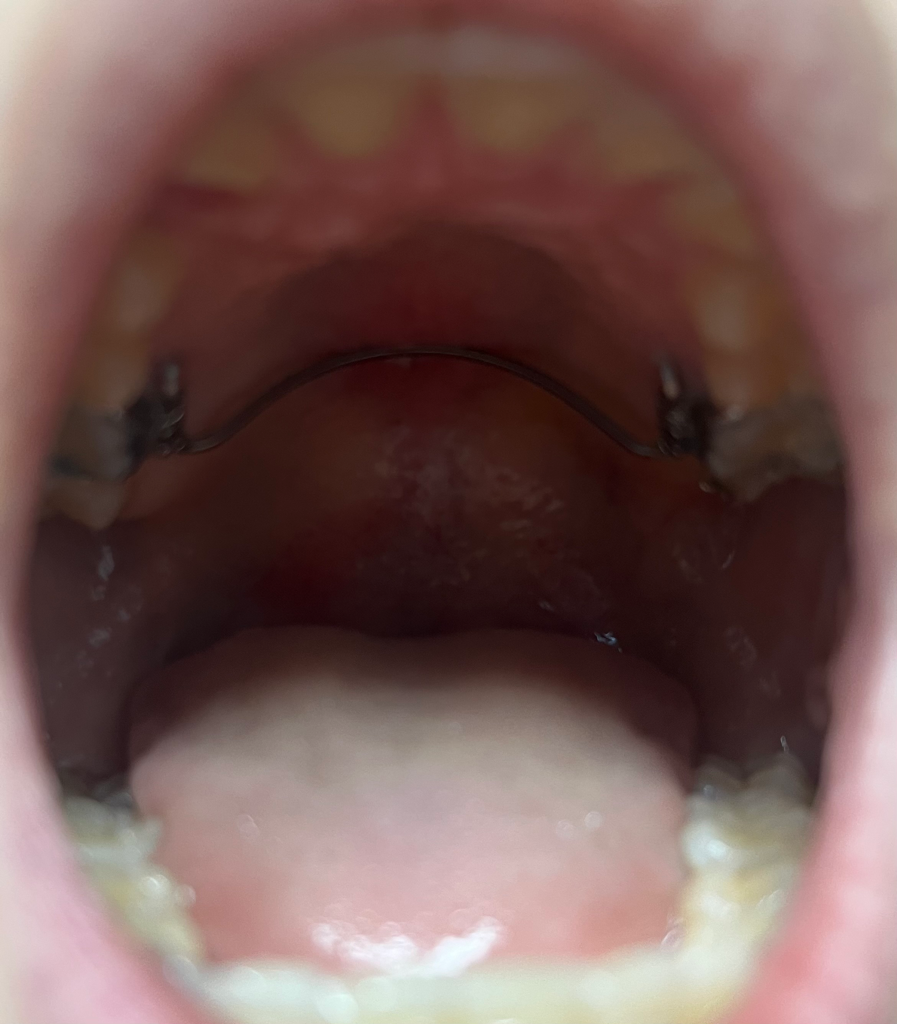

악궁확장장치가 입천장에 딱 붙어 통증이 생겼어요. 월진료 전인데 병원에 가야할까요?

이렇게 생긴 악궁확장장치를 7개월 정도 하고 있습니다. 최근에 반지 낀 이가 너무 아프고, 밥 먹을때 장치가

덜그럭 거리더니 악궁확장장치 아치(?)부분이 입천장에 딱 붙었어요. 점점 통증이 생겨 밥 먹기가 너무 불편해지고 있는데, 월진료 전인데 병원에 가야할까요?

• 1번 째 사진